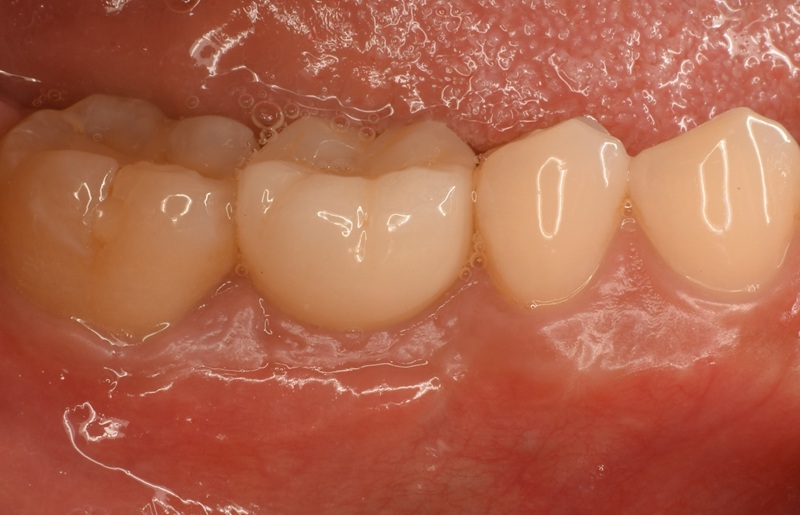

| 治療名 | GBRとインプラントを行った症例 |

| 治療説明 | インプラントを埋入予定の部位において、骨の吸収が見られたため、インプラント埋入と同時に小規模な骨造成(GBR)を行いました。治癒期間を経て、最終的にセラミックの上部構造を装着し、自然な見た目としっかりとした噛み合わせを回復しました。 |

| 治療回数・期間 | 6ヶ月 |

| 副作用とリスク | インプラント治療は、入れ歯やブリッジに比べて治療期間が長くなる傾向があります。骨造成が必要な場合は、さらに治療期間が延びることがあります。 また、手術後には一時的な違和感や痛み、腫れ、出血などが生じる場合がありますが、通常は2日〜1週間ほどで落ち着きます。 |

| 料金(税込) | GBR〈小規模骨造成〉:110,000円 インプラント一次手術:220,000円 二次手術:55,000円 上部構造〈セラミック〉:165,000円 合計:550,000円 |